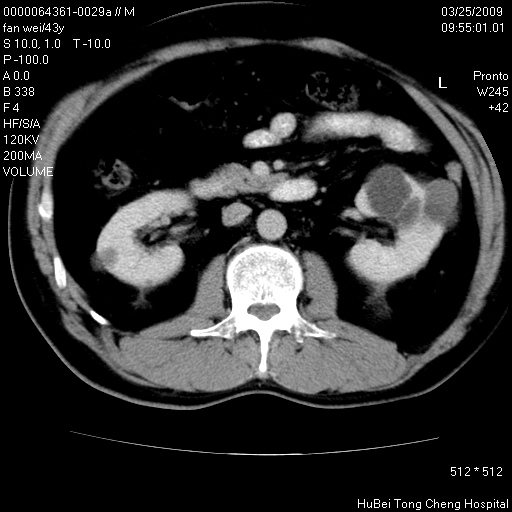

双肾ct轴位平扫+增强扫描(层厚10mm,螺距1.0,重建间隔10mm),图像如下:

双肾多发性囊肿

左肾体积变大,支持多囊肾。

双侧多囊肾!

双肾多发性囊肿   脂肪肝

囊肿数得清,肾功能正常,考虑多发肾囊肿.另外,右肾后极突向肾周间隙的那个病灶是不是错构瘤,请楼主调窗看看.